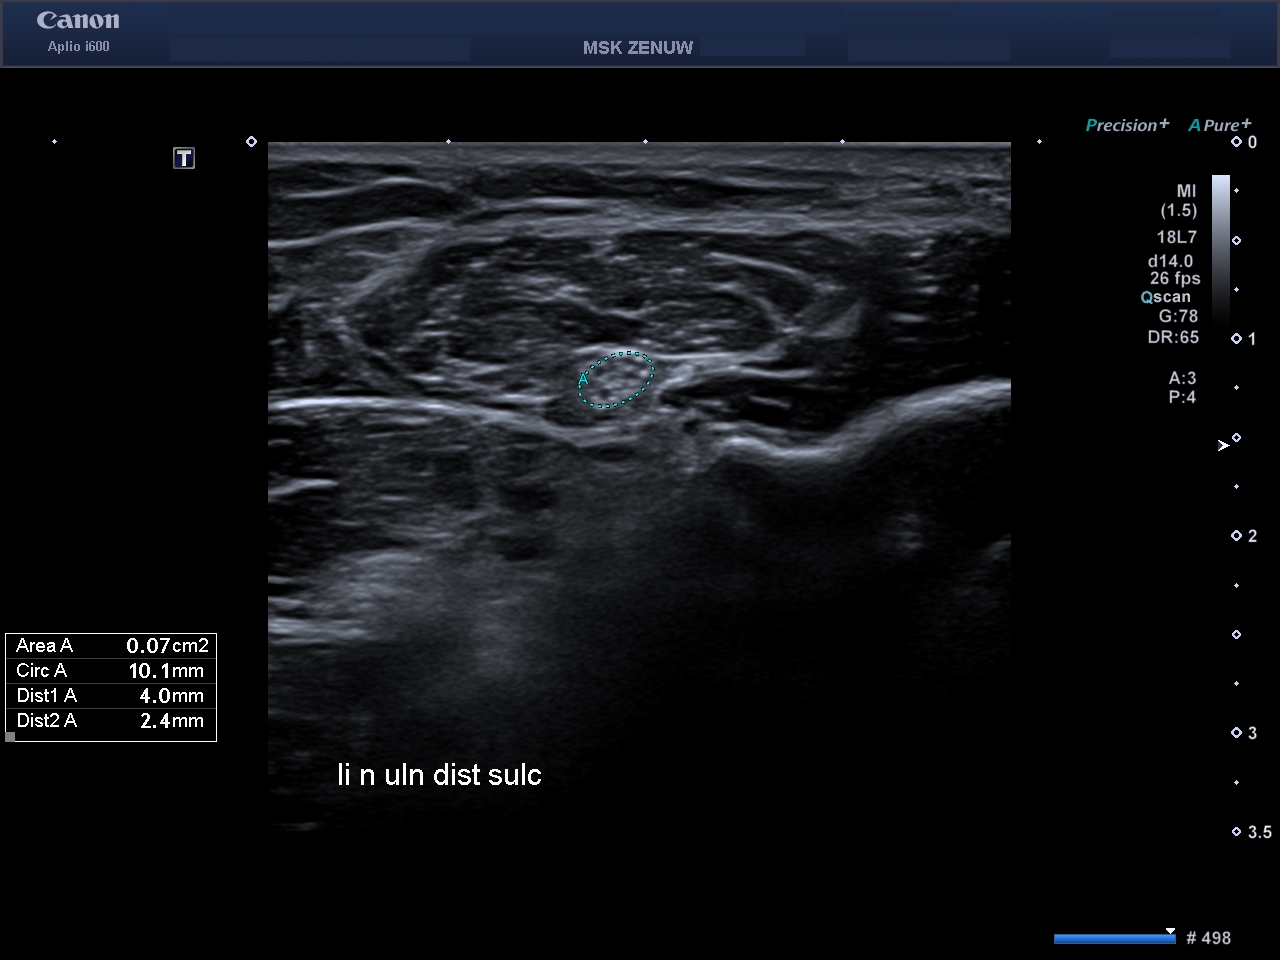

Представляємо вам клінічні випадки візуалізації періферійніх нервів на Aplio i800 з використанням високочастотного датчика 24 MHz. Ці приклади яскраво говорять самі за себе.